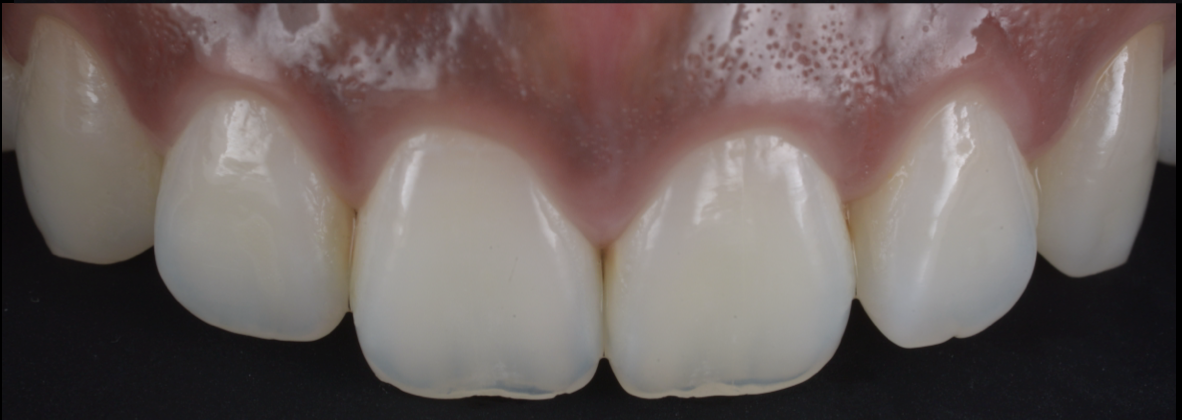

治療前

治療後

| 治療内容 | ラバーダム、マイクロスコープ、 MTAを用いた精密根管治療 歯根端切除術 |